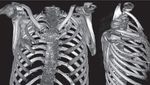

Jakarta - Begini penampakan pisau yang menancap di dada seorang pria di Tanzania. Pasien baru menyadari di tubuhnya ada pisau 8 tahun kemudian.

Foto-foto Penampakan Pisau Menancap di Dada, Pasien Sadar Setelah 8 Tahun